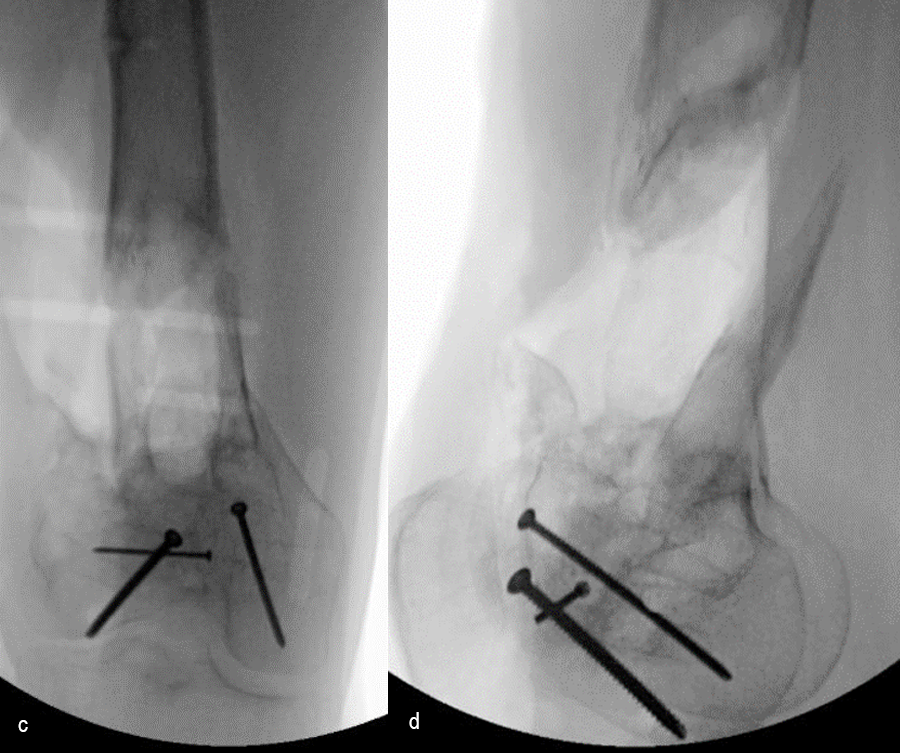

The day following admission, the patient underwent these procedures in the operating room (Fig 6):

> Washout of open injuries right side, including femur and ankle

> Open reduction of the talar injury

> Spanning external fixator of the femur and ankle

> External fixation of the left plafond/talus

At 3 days postoperative, the patient underwent a repeat washout of the right femur and right ankle. The lung injury was still recovering so no definitive fixation was performed at this time.

At 5 days post-initial surgery, the lung injury was improved, so the patient underwent open reduction and internal fixation (ORIF) of the right distal femur with resection of devitalized bone and cement spacer placement (Fig 7). Definitive fixation of the other fractures (ankle and ribs) was undertaken over time.